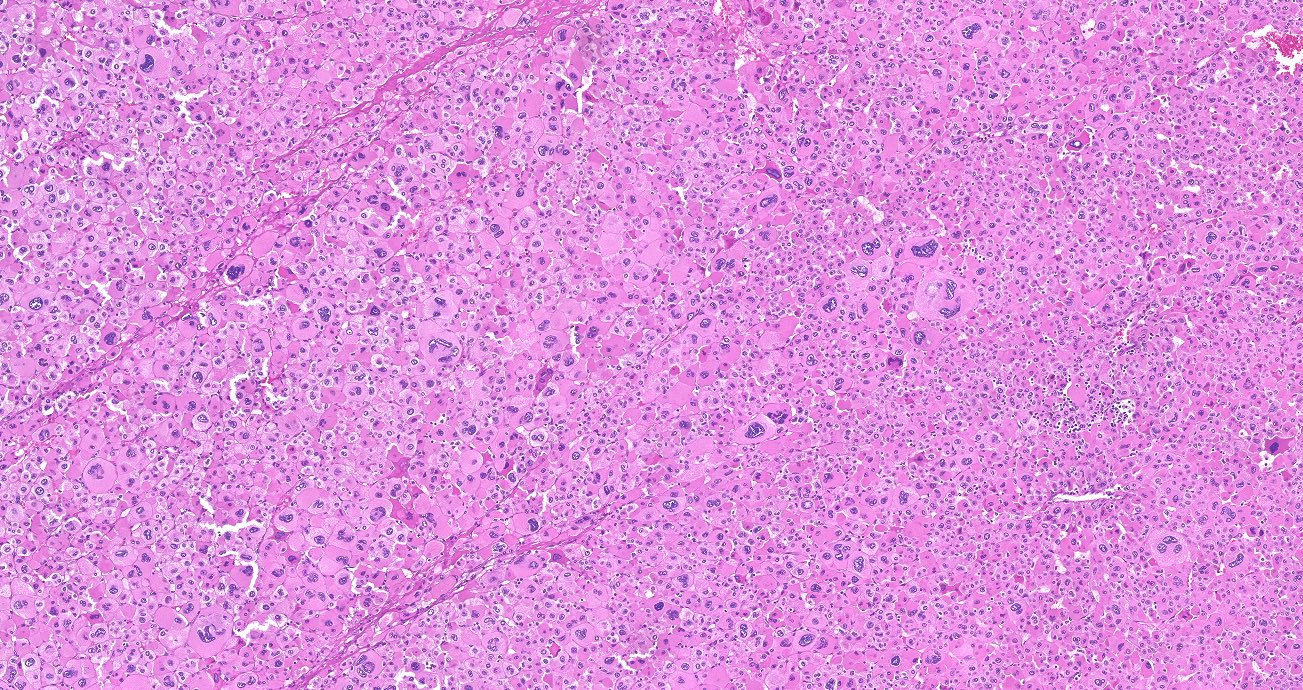

Microscopic (histologic) description

- In comparison to surrounding adrenal gland, adenoma cells are larger with different cytoplasm, increased variation in nuclear size

- Distinct cell borders, cells have abundant foamy cytoplasm reminiscent of zona fasciculata

- Balloon cells: clusters of cells with enlarged lipid-rich cytoplasm (seen in Cushing syndrome)

- Histologic variants: oncocytic, myxoid

Microscopic (histologic) images

Contributed by Xiaoyin "Sara" Jiang, M.D., Debra Zynger, M.D., @Andrew_Fltv on Twitter and @SueEPig on Twitter